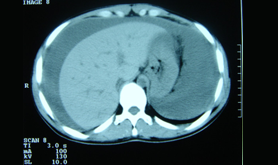

The CT scan of the abdomen is a very important medium by which one can manage abdominal disorders. The high resolution powers of the scanners make it possible to demonstrate the anatomy of the abdominal region and its associated ailments.

The CT Abdomen plain is used to figure out the defects in the abdomen by diagnosing the cause of the abdominal pain and disease of the internal organs, small intestine and colon which can be caused by any of the following: